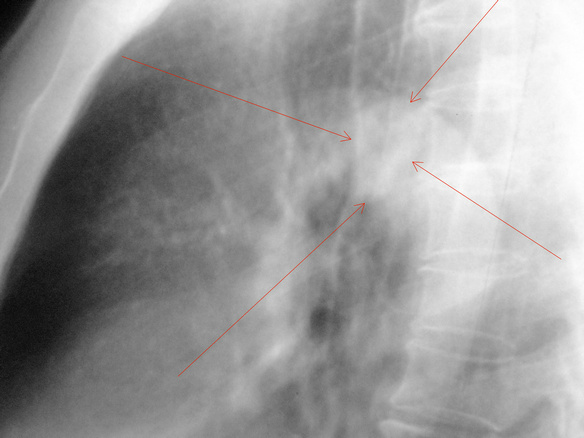

男.66.慢支炎数年.请会诊

右下肺结节是否乳头影透视一转一目了然,至于右肺门区软组织影,可结合ct检查,既然觉得不正常就不要放过,没事大家都放心,别留遗憾。

透视一下或者做一个ct,感觉有占位。